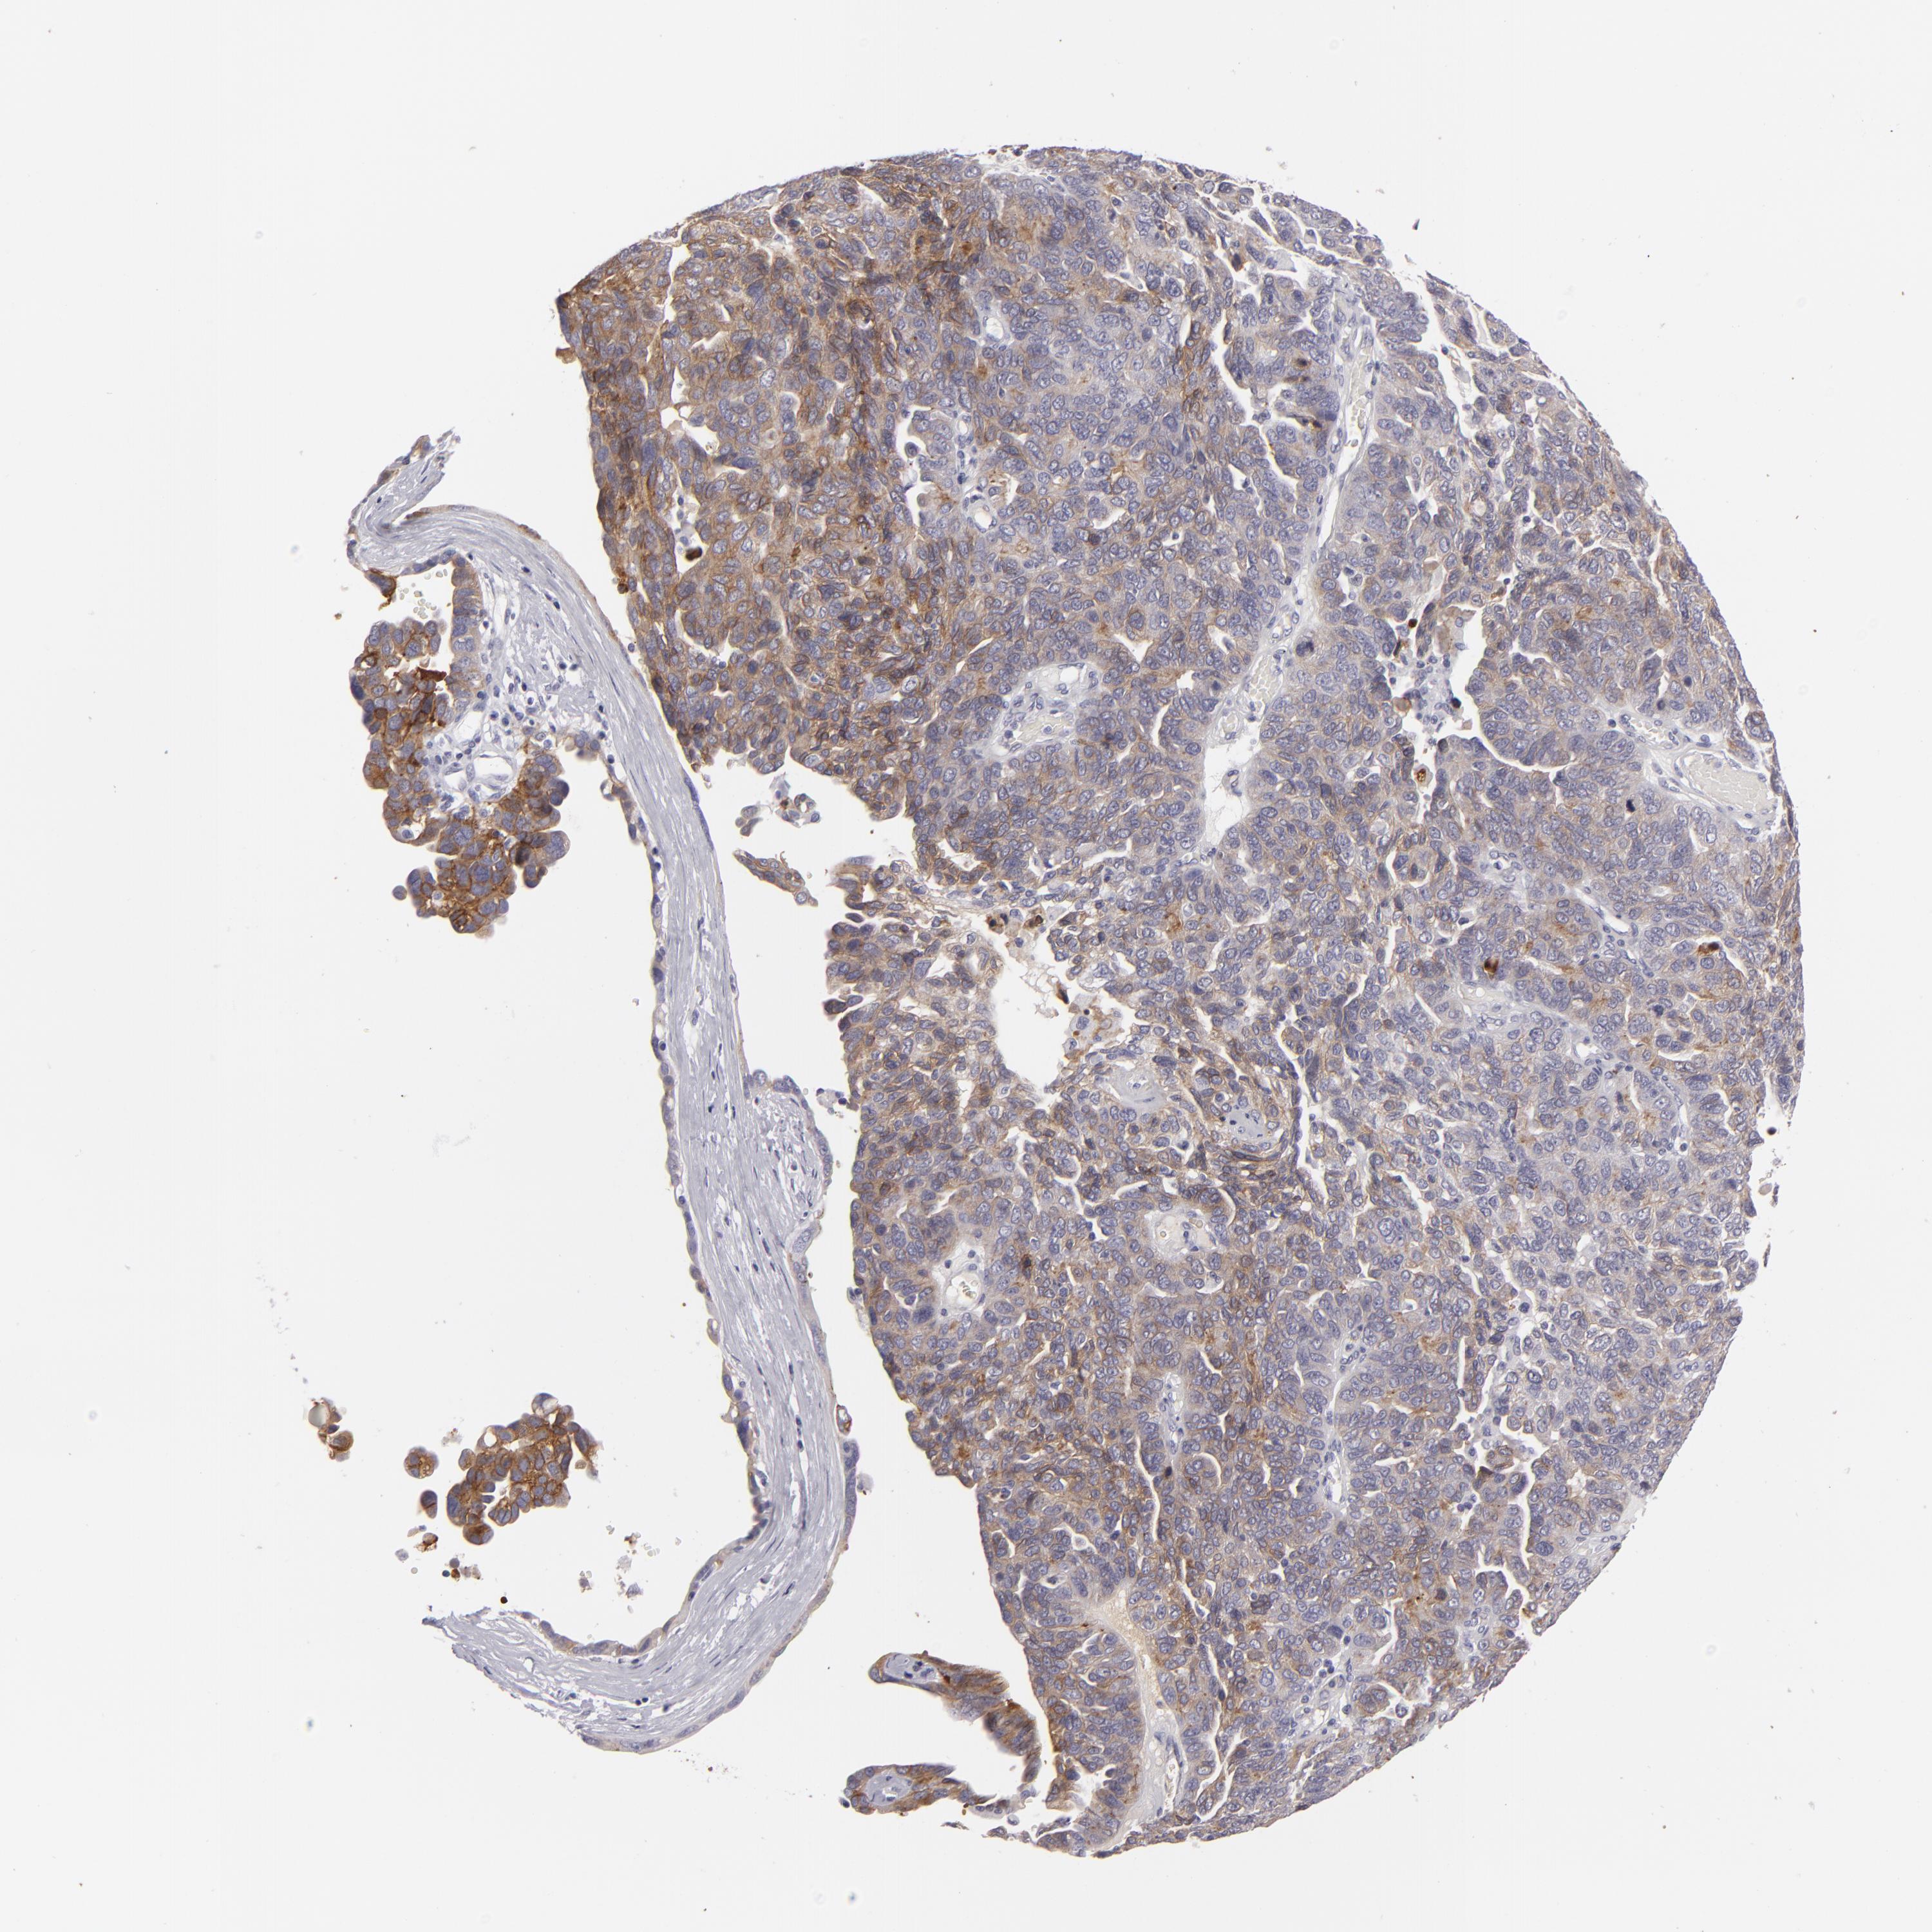

OVARIAN CANCER - Protein expressioni

A mouse-over function shows sample information and annotation data. Click on an image to view it in a full screen mode. Samples can be filtered based on level of antibody staining by selecting one or several of the following categories: high, medium, low and not detected. The assay and annotation is described here.

Note that samples used for immunohistochemistry by the Human Protein Atlas do not correspond to samples in the TCGA dataset.

Antibody stainingi

Antibody staining in the annotated cell types in the current human tissue is reported as not detected, low, medium, or high, based on conventional immunohistochemistry profiling in selected tissues. This score is based on the combination of the staining intensity and fraction of stained cells.

Each image is clickable and will lead to virtual microscopy that enables deeper exploration of all samples and also displays staining intensity scores, fraction scores and subcellular localization as well as patient and tissue information for each sample.

Antibody HPA032047

Antibody CAB002139

Staining

High

Medium

Low

Not detected

Intensity

Strong

Moderate

Weak

Negative

Quantity

>75%

75%-25%

<25%

None

Location

Nuclear

Cytoplasmic/membranous

Cytoplasmic/membranous,nuclear

Cystadenocarcinoma, serous, NOS

Carcinoma, endometroid

Cystadenocarcinoma, mucinous, NOS

Carcinoma, NOS